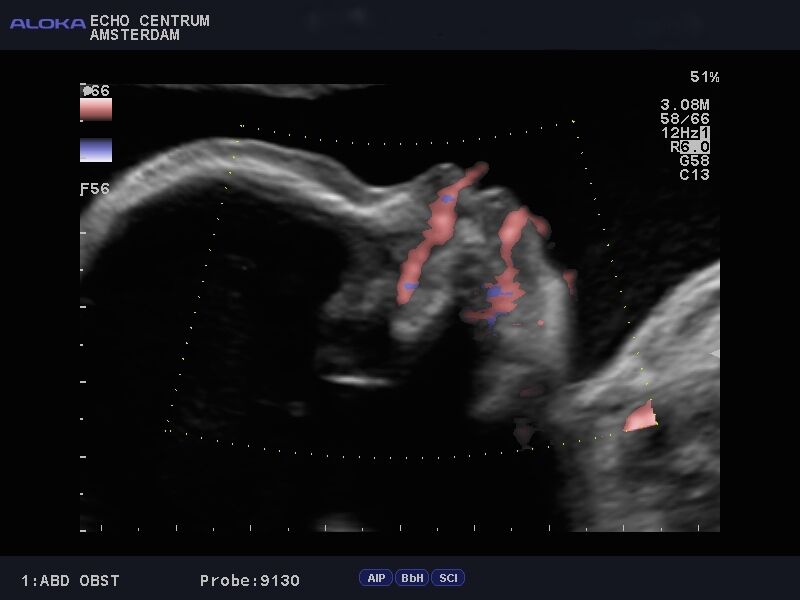

Onlangs had ik een hele leuke ervaring. Ik ben een gepensioneerd gynaecoloog, en was vroeger zeer begaan met mijn verloskundige patiënten. Mijn schoondochter en zoon nodigden mij uit om mee te gaan naar een "pretecho"van dr. Papa in Amsterdam. Wij, gynaecologen, hebben geweldige vooroordelen tegen een zogenaamde pret echo en vinden ze vaak overbodig. Nou dit pakte anders uit. We werden verwelkomd door een bijzonder charmante, leuke en vlot bespraakte Nederlandse Antiliaan: Elvin Papa, arts echoscopist. Daar zat hij in zijn spreekkamer, in een prachtig pand, achter een prachtig echo apparaat, dat voor mijn toenmalige ziekenhuis te duur was om voor ons gynaecologen aan te schaffen!! Alles werd getoond, het hele lichaampje van de baby. Alle organen, het geslacht, hart en bloedvaten noem maar op. Prettig was dat je in 3D een hele goede indruk krijgt van het gezichtje. Het hele onderzoek verliep voorspoedig en was heel relaxed. Papa doet veel aan nascholing en houdt de ontwikkelingen op echo gebied heel goed bij. Echo onderzoek kan heel vervelende zaken aan het licht brengen. Wij hadden een goed nieuws echo, dus dat is feest en lol. Belangrijk lijkt mij wel dat je met een slechte echo bij Elvin Papa in goede handen bent. Hij zal weten hoe je te troosten en hoe je door te verwijzen. Hopelijk hoeft dat niet vaak. Ik wens hem nog veel succes toe.

Bij deze willen wij je nog even bedanken voor de mooie en bijzondere echo die je van onze tweeling hebt gemaakt (de echo lukte zo goed!). Aangezien we ons nogal veel zorgen maakten was de echo precies de positieve input die we nodig hadden. We zijn natuurlijk een beetje beroepsgedeformeerd en wij vonden het schitterend dat je met de moderne technieken (je superecho-apparaat!!) de anatomie van die piepkleine mensjes zo goed kunt zien! Nogmaals ontzettend bedankt.